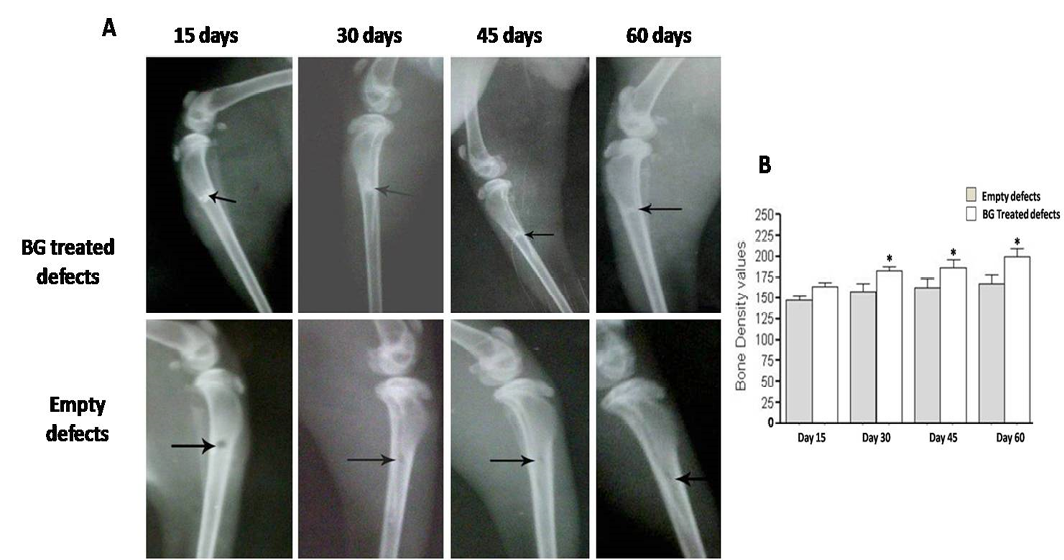

Radiographic evaluation displays complete bony regenerate throughout defects treated with silicate 45S5 BG (A) in addition to significant increase in radiopacity (B). *P<0.05